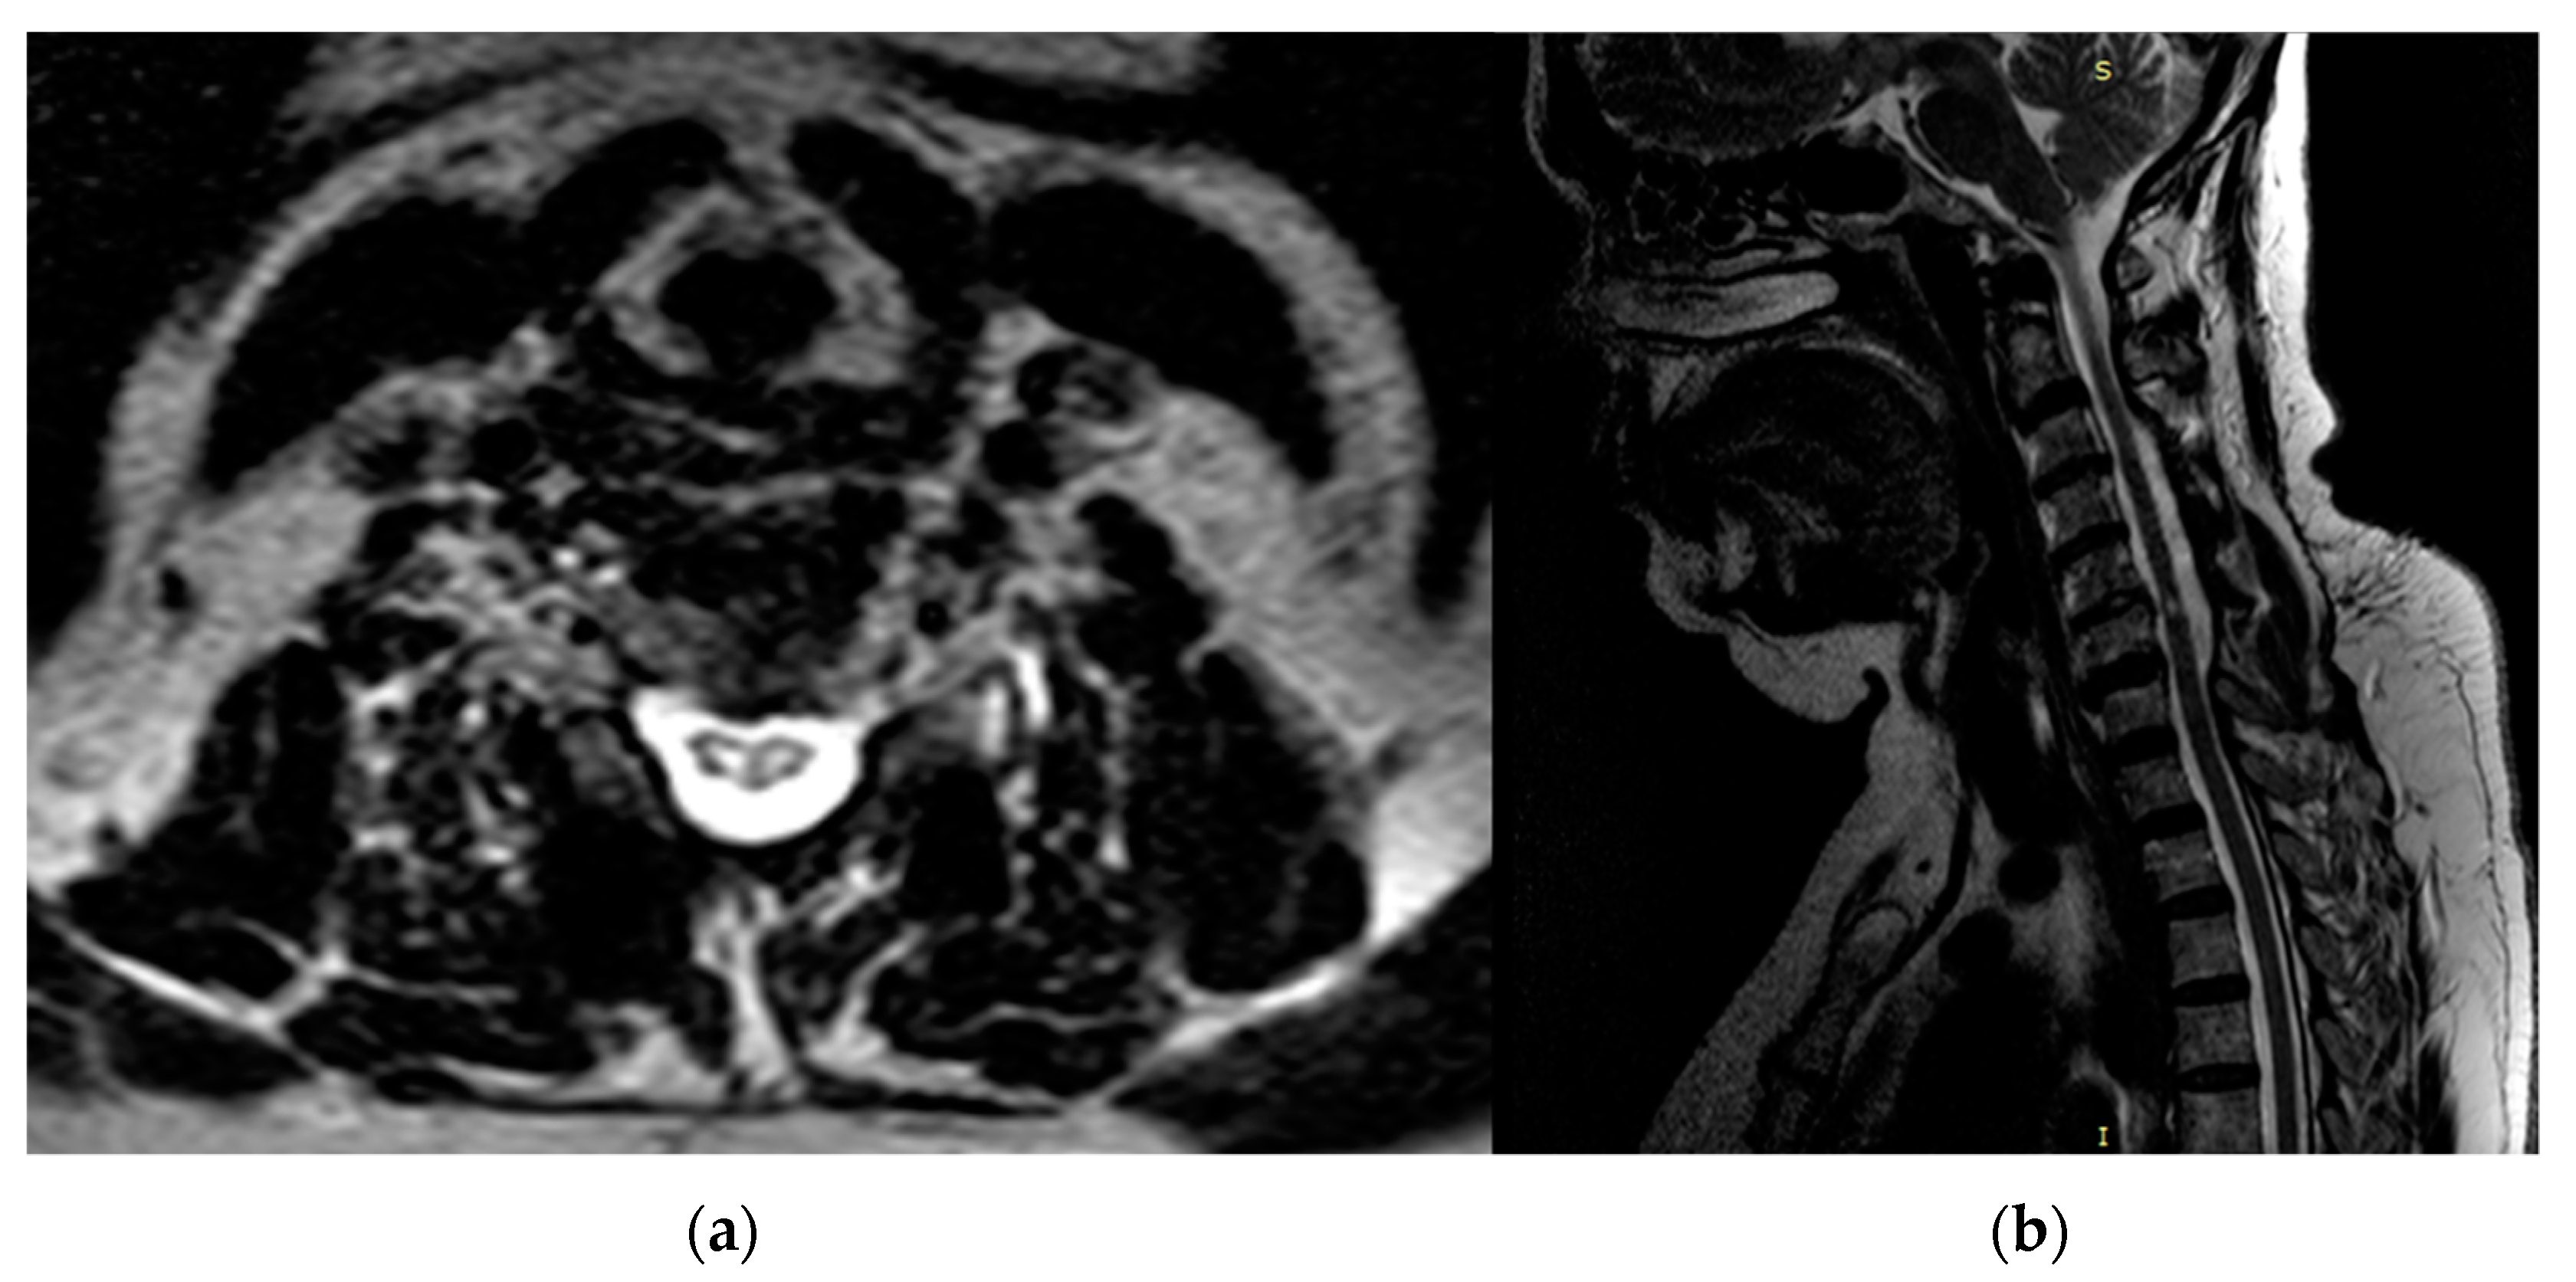

| Reporting results | Regarding DCM, the “snake-eye” appearance was regarded as a negative prognostic factor in 144 cases. In particular, in Mizuno’s study, the improvement ratio determined by JOA score was 32.2% in SEA (mean post-operative mJOA score of 12.9), 47.1% in non snake-eye appearance (NSEA), and 50% (p < 0.01) in control cases in which high signal intensity was absent. |